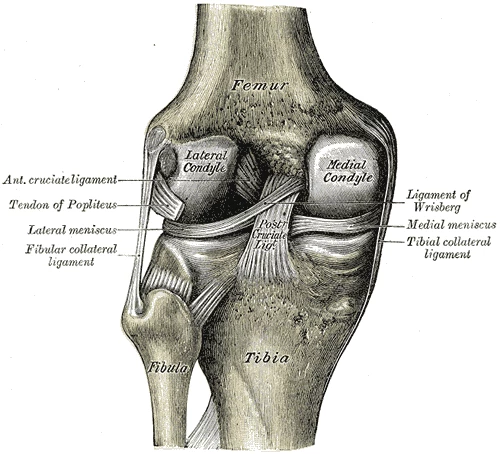

Degradation of the knee cartilage can be brought on by all sorts of causes – trauma, hereditary and developmental factors or even just plain wear and tear – but the result is the same. Without healthy cartilage cushioning the point where the femur sits on top of the tibia, those two bones grind away at each other with the full weight of the body behind them, causing painful and incapacitating damage over time.